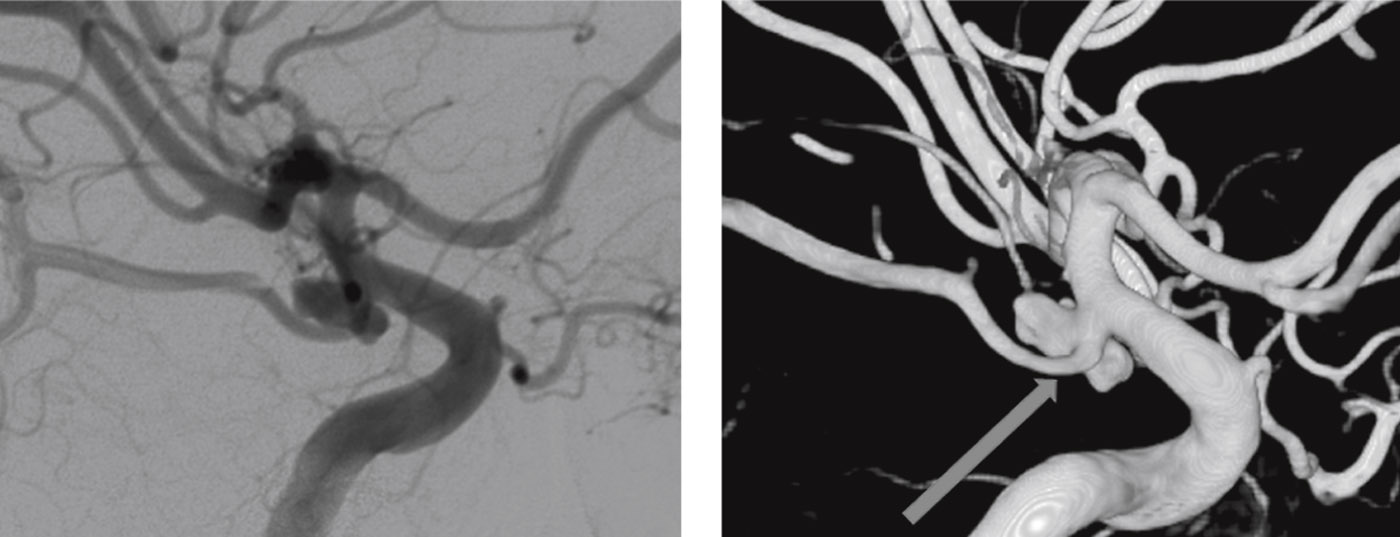

Despite the advances in MR-imaging, the DSA remains the diagnostic gold standard for the diagnosis of intracranial aneurysms (ruptured or unruptured). It allows detailed visualization of the morphology – neck, dome, lobules, «baby aneurysms» or blebs as well as the morphology of the blood inflow jet and impact on the dome – that help to better estimate the rupture risk of UIA (Figure 3). Moreover, the DSA helps to select the treatment modality and estimate the treatment risk by identifying perforating arteries from the aneurysm and determine the collateral circulation. As it is an invasive diagnostic procedure with a risk of neurological complication of about 0,1% the DSA should be reserved for those patients with UIA that are considered potentially dangerous by experts.